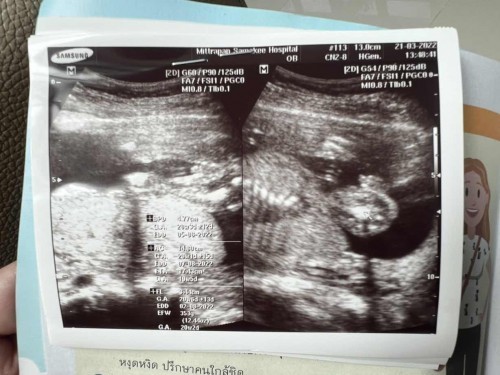

ช่วยดูหน่อยค่ะว่าน้องเพศอะไรคะ ซาวด์ตอน20week2day

หมอบอกผู้ชายค่ะ แต่ไม่100%